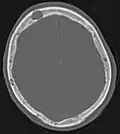

Scanner d'une métastase ostéocondensante dans l'os du crâne d'un patient souffrant d'un carcinome de la prostate. On reconnaît clairement l'extension de la métastase au-delà des limites initiales de l’os.

Par comparaison, scanner de métastases ostéolytiques dans l'os du crâne d'une patiente souffrant d'un cancer du sein. On distingue une ostéolyse plus grande sur le front, et plusieurs plus petites.